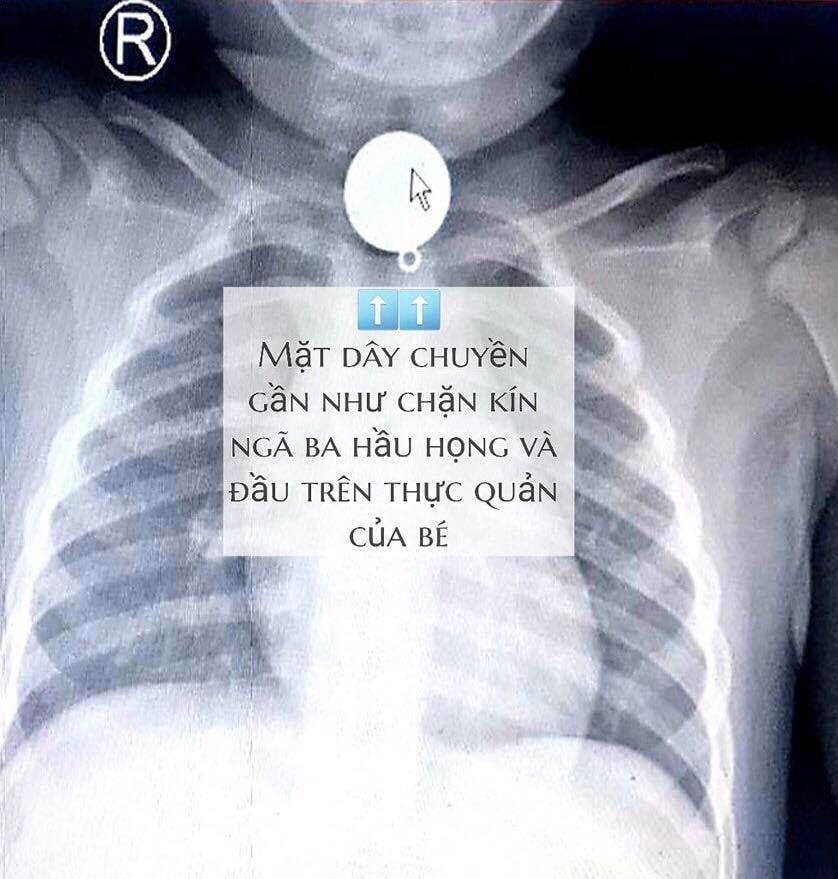

Tại bệnh viện, sau khi hội chẩn xác định dị vật mắc trong cổ bé rất to, hình tròn nằm chiếm hết lòng đầu trên thực quản, gần ngay ngã ba thông với đường thở, các bác sĩ nhận định khả năng dị vật gây trầy, rách thực quản, hay hóc ngược vào đường thở rất cao nếu xử trí không khéo.